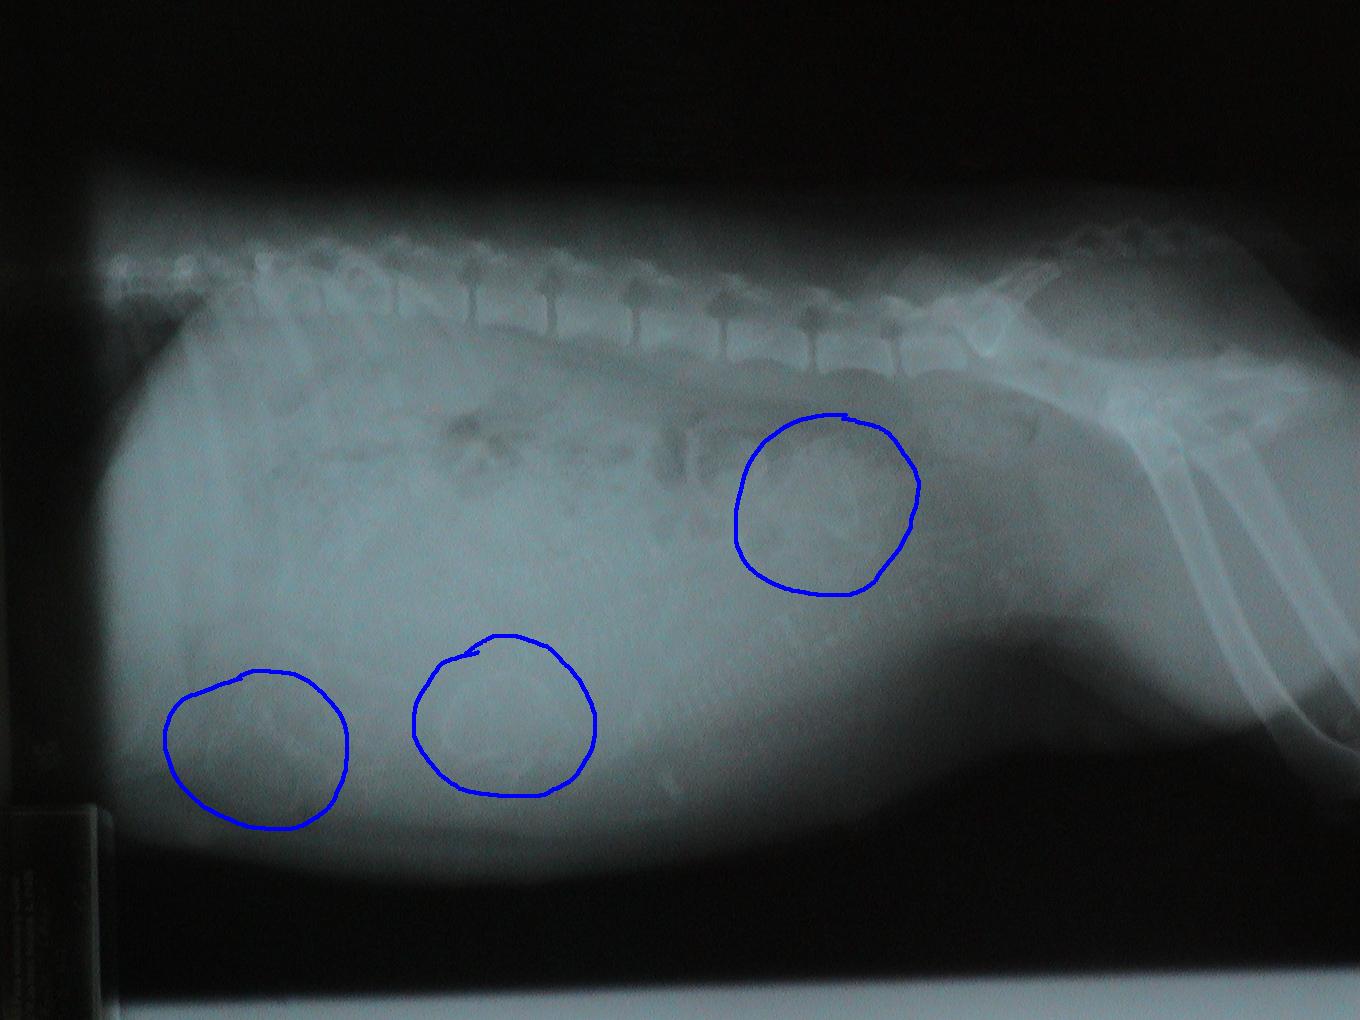

This is a trick question. This is a pregnant dog. Each skull is circled in blue.